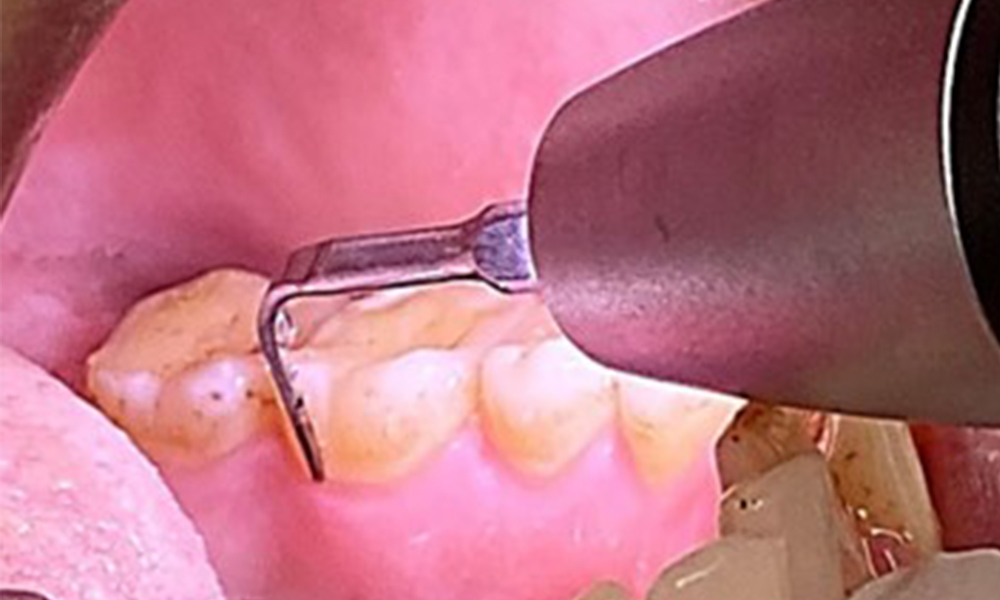

The objective would be to control disease risk by removing supragingival and subgingival biofilm. The instruments can be selected based on patient needs. First, calculus and any concretions must be removed using ultrasonic and/or manual instruments (Fig. 10).

Use of a piezo-driven ultrasonic device in the lingual area near 36

Fig. 10 Use of a piezo-driven ultrasonic device in the lingual area near 36 (Proxeo Ultra, W&H, shown here), © Dr R. Krapf